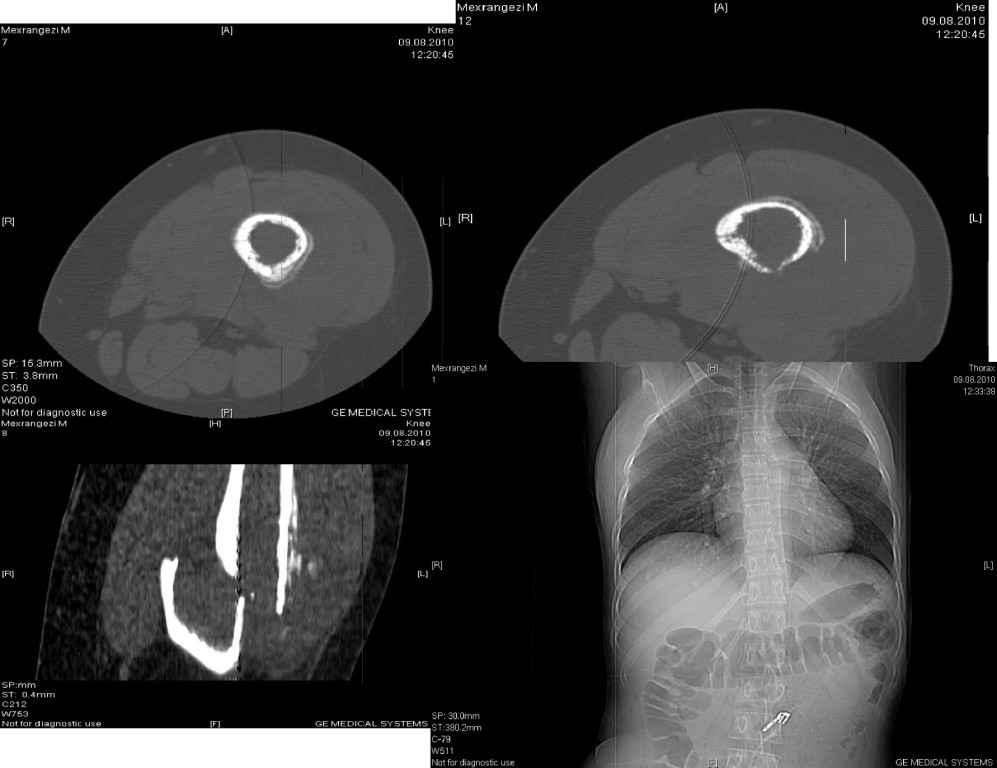

больной 18 лет, студентка I курса медуниверситета. Травма исключается, во время ходьбы почувствовала боли в области с/3 правого бедра и упала. Со слов в течени последних 2 месяца появилось опухоль в области с/3 правого бедра.

Имеется мягкотканный компонент на бедре. Снимки во вложении.Наш предварительный диагноз после консультации онколога: Саркома бедренной кости с двухсторонним поражением легкого.(Рентгенолог указывает на МТС легких).